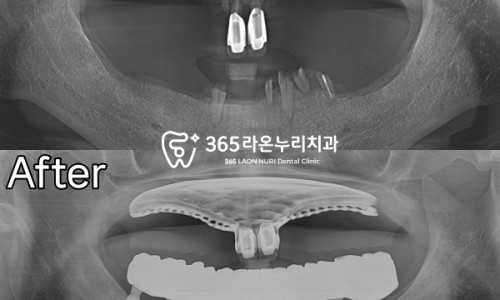

그래서 환자의 동의하에 하악은

전악 식립을 마친 모습인데요,

치조골의 두께를 파악하여

중앙에 잘 심어드렸으며

가이드를 이용하여 오차 발생을 줄이고

잇몸도 크게 절개하지 않았기에

통증도 크지 않으셨다 합니다.

2개월 정도 임시 보철을 사용하면서

회복을 기다렸으며

그 이후에 최종 보철물을 올려드렸습니다.

상악은 틀니 하악은 임플란트인 만큼